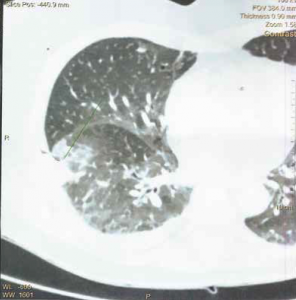

Moult traitements antibiotiques et pourtant, une bronchite qui persiste…

De quelle manière allez-vous prendre en charge cette patiente ? Introduction Mme M. est une patiente de 70 ans qui vient nous consulter, car depuis plus d’1 mois elle présente une…